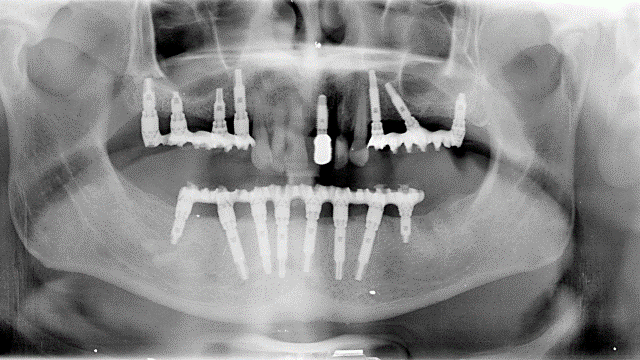

L'implantologia diventa quindi in questo ambito riabilitativo l'alternativa per eccellenza, in quanto permette il ripristino totale della funzione masticatoria con denti fissi. Tale protesi completa con impianti, è conosciuta come "Toronto Branemark Bridge" e prevede secondo il protocollo svedese originale, l'inserimento di un numero adeguato di impianti nelle arcate ed in posizioni idonee tali da sostenere meccanicamente la successiva protesi fissa ed il relativo carico masticatorio (almeno 6 nell’arcata superiore e 5 nell'inferiore). Relativamente al numero di impianti che sono necessari per soddisfare le condizioni meccaniche utili ad applicare su di essi una protesi fissa, negli ultimi anni è venuta a mancare la consueta chiarezza. Come detto poco sopra il protocollo svedese originale recita testualmente:

nell’arcata superiore “almeno sei impianti nell’area della premaxilla, ovvero l’area ossea compresa tra i seni mascellari da entrambi i lati”

nell’arcata inferiore “cinque impianti nella regione del mento, entro i limiti anatomici determinati dal nervo mentoniero”.

Numerose sono pertanto le combinazioni terapeutiche le quali conseguono interamente dalle caratteristiche anatomiche dei mascellari superiore ed inferiore relativamente alla disponibilità dei volumi ossei residui ed alla loro forma geometrica.